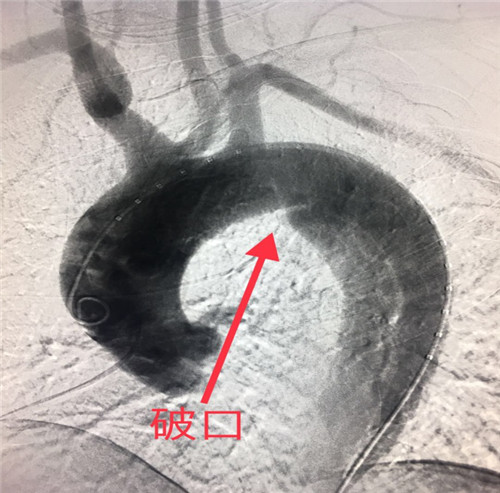

患者,男性42岁,患高血压数年,常年在外务工,以“突发剧烈背痛”在当地医院就诊并行胸部CT平扫及胸主动脉血管成像检查,CTA提示主动脉夹层、破口位于左锁骨下动脉远端,诊断为主动脉夹层,患者家属电话与乐鱼在线登录入口介入科李建国主任联系,由当地120转入我院,患者胸背部剧烈疼痛、情绪血压极不稳定,随时有破裂死亡风险,命悬一线。李建国主任反复叮嘱,在转院途中务必控制好心率、血压。

经过紧锣密鼓准备,于2018年6月3日为患者在局麻下成功施行了介入胸主动脉夹层覆膜支架腔内修复术。

胸主动脉夹层起病急、发展快、死亡率极高,若不及时有效治疗,48小时内死亡率70%左右,一周内的死亡率高达90%左右。该患者胸主动脉夹层破口距离左锁骨下动脉开口不足1厘米,为患者实施覆膜支架成功修复腔内破口、部分保留左锁骨下动脉避免了术后出现左上肢无脉症、脑缺血等严重并发症,该术式是目前主动脉夹层介入治疗的首选,较传统外科开胸手术创伤大、高风险、术后恢复慢,介入覆膜支架植入术具有微创、高效、安全等优势。